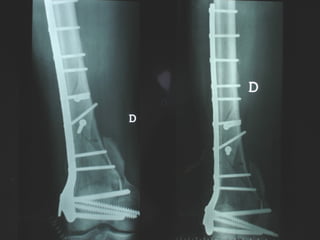

INDICAZIONI COMUNI Fratture sovracondiloidee Fratture intercondiliodee Fratture diafisarie distali PARTICOLARI Fratture con grave osteoporosi Fratture periprotesiche

VANTAGGI CHIRURGIA MININVASIVA Mini Open Inserimento della placca sottocutaneo per scivolamento Viti percutanee Preservazione dei tessuti molli Ridotto danno vascolare Rapida ripresa funzionale

LISS  NCB

NCB

Conclusioni Riduzione  anatomica Minimo trauma chirurgico Corretto equilibrio fra elasticità e stabilità Precoce mobilizzazione